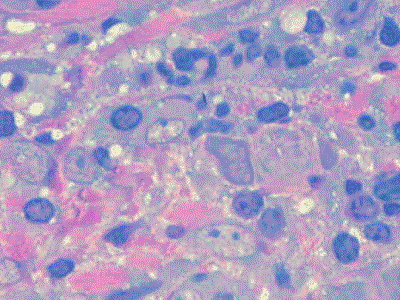

| Respuesta inmune El epitelio de unión y el epitelio de la bolsa son muy

permeables a moléculas

grandes que activan una reacción inmune en el tejido conjuntivo

gingival . En las fases tempranas en

esta reacción predominan los linfocitos para luego aparecer las

células plasmáticas y en

forma tardía predomina la infiltración inmune. La reacción inmune

genera los mediadores que refuerzan la inflamación y el daño al

tejido. En particular la producción de citoquinas

es prominente. Estas substancias son moléculas muy

potentes que activan varios

eventos perjudiciales en

el tejido conjuntivo.

La inflamación

y las reacciones inmunes de la gingiva y el periodonto resulta en

que dichas estructuras funcionales son reemplazadas por tejido de

granulación, que continúa

creciendo apicalmente, facilitando

el desarrollo de placa bacteriana en la bolsa periodontal.